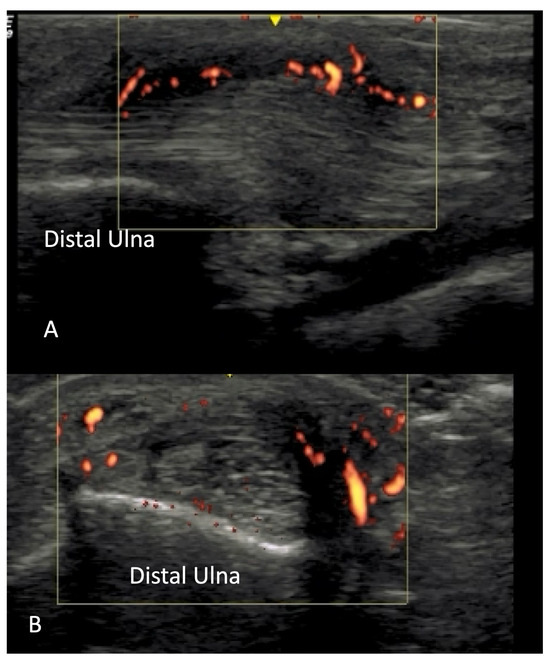

2.4. Vascular Pathology

4.2. Evaluation of the Wrist

4.2.3. Ulnar Aspect